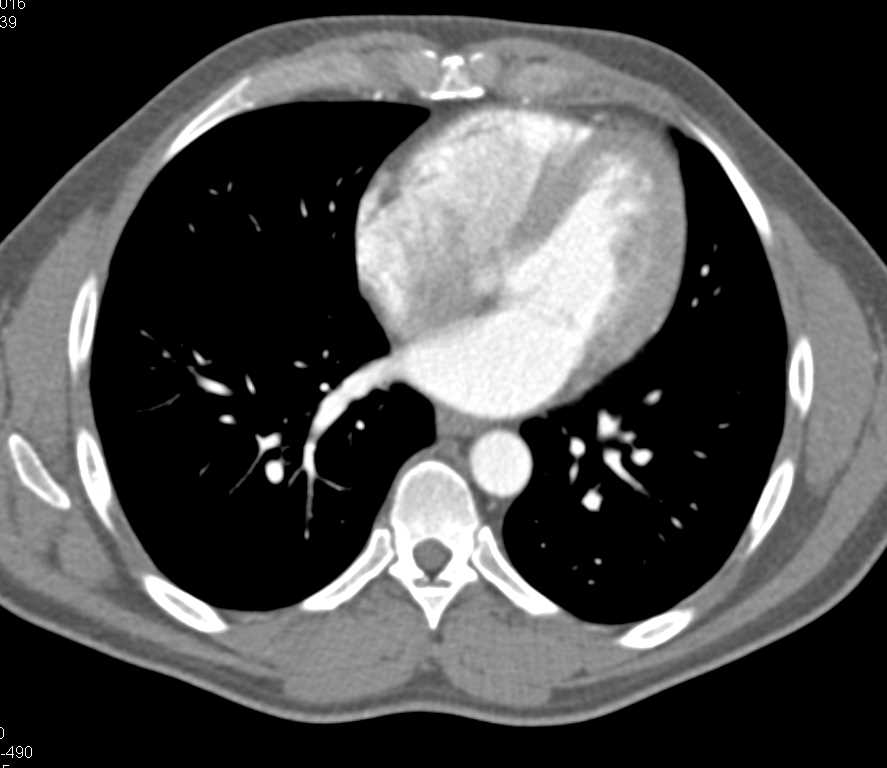

Stent in Left Iliac Vein and Inferior Vena Cava (IVC)